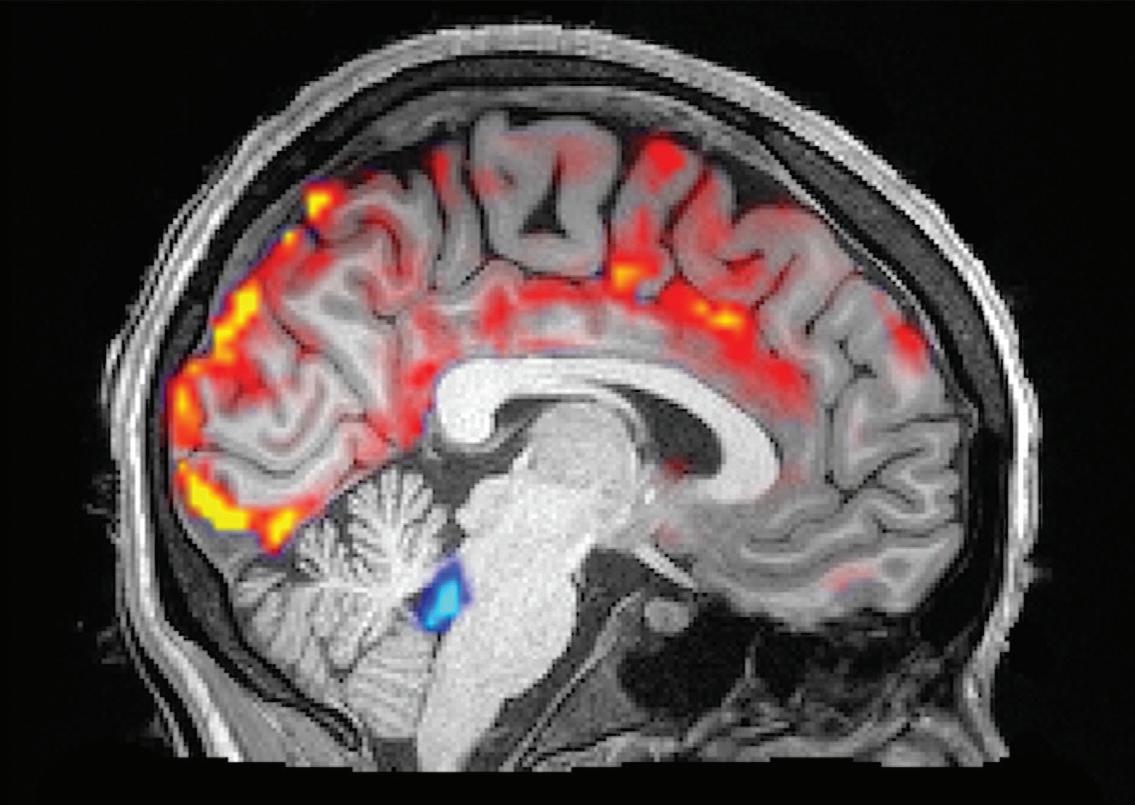

They did this by scanning subjects with functional MRI while showing them videos with either faces approaching them and appearing to violate personal space boundaries — thus triggering the sensitivity to social threat that has been associated with loneliness — or faces moving away from them, signaling social withdrawal.

In fact, the study revealed an association between loneliness and a greater response to the withdrawing faces in the hippocampus and a related network of subcortical brain regions involved in emotion and homeostatic regulation. This pattern of responses was similar across the psychotic disorder and healthy control groups, suggesting that it may represent a marker of loneliness.

“Understanding how the brain responds when a person’s social needs are not being met gives us an objective way to measure and monitor this type of deficit,” says Dr. Holt, “which will help us understand the effects of loneliness on the body and how to reverse those effects.”